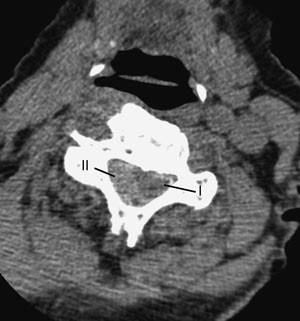

Lumbal spinalpunksjon ga blank spinalvæske med normal dråpetakt og normale verdier for celler, protein og glukose. Pasienten kunne ikke undersøkes med MR grunnet pacemaker. CT av cervikalcolumna viste ingen skjelettskade, men ga heller ingen forklaring på myelopati. Røntgenmyelografi med intratekal kontrast via lumbalt innstikk viste spinalt blokk i nivå C6 (fig 1). Etterfølgende CT avdekket en romoppfyllende prosess bak og til høyre for ryggmargen i samme nivå, som presset ryggmargen mot venstre (fig 2). Ved sagittal (fig 3) og koronal rekonstruksjon så man utstrekningen av prosessen opp til overgangen C2/C3.